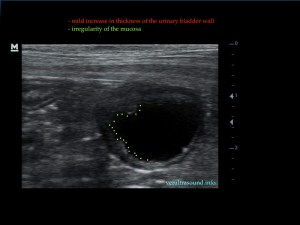

Η πάχυνση του τοιχώματος και η δοκίδωση του βλεννογόνου είναι εμφανής σε όλες τις εικόνες. Πολλές φορές οι λαγόνιοι λεμφαδένες μπορεί να είναι ήπια διογκωμένοι και να έχουν αντιδραστική ηχομορφολογία. Ο έλεγχος με έγχρωμο Doppler του τοιχώματος της άδειας κύστης μπορεί να μας δείξει ροή αίματος στα αγγεία της κύστης. Αντίθετα, είναι πιθανό, όσο η κύστη γεμίζει με ούρο η ροή αίματος να μην είναι ορατή με το Doppler. Αυτό συμβαίνει συχνά στη χρόνια βακτηριακή κυστίτιδα λόγω της ίνωσης του τοιχώματος της ουροδόχου και αυτή είναι μία από τις αιτίες της μη ανταπόκρισης στη θεραπεία. Η συγκεκριμένη παθοφυσιολογία έχει μελετηθεί στον άνθρωπο με την βοήθεια ενδοσκοπικού υπερήχου.

The increase of thickness of the urinary bladder wall and the striation of the mucosa is evident. Inguinal lymphnodes are usually prominent and mildly enlarged. Colour Doppler may reveal the blood flow of the mucosa of the empty urinary bladder, whereas the blood flow in a full bladder appears decreased. This could be because of the fibrosis of the urinary bladder wall and could explain why sometimes chronic conditions like these do not respond well to antibiotics. This pathophysiology has been studied in humans with the use of endoscopic ultrasound.